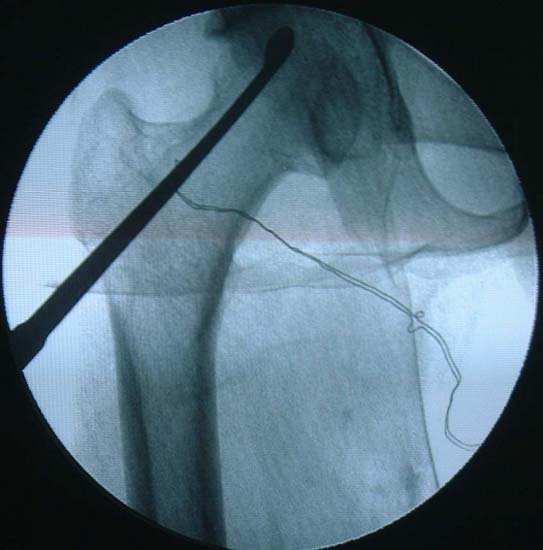

早、中期的股骨头坏死治疗的首选方法仍是“保头”。我们采用最新的组织工程学原理,将复合骨生长因子和自体骨髓干细胞的新型植骨材料,植入骨坏死区。既可刺激新骨形成,又增加了对软骨下骨的机械支撑力,从而有效地防止了股骨头的进一步塌陷。创伤轻微,切口仅为3—5CM,不损伤关节囊血液循环,关节活动功能好。对年轻的、中早期股骨头坏死的治疗有极大价值。

股骨头缺血性坏死MRI显示坏死区 微创手术方法,刮除死骨

复合骨生长因子和自体骨髓干细胞的新型植骨材料植入支撑,恢复形态, 手术后24个月X线片,关节塌陷未加重,关节功能良好,无疼痛。